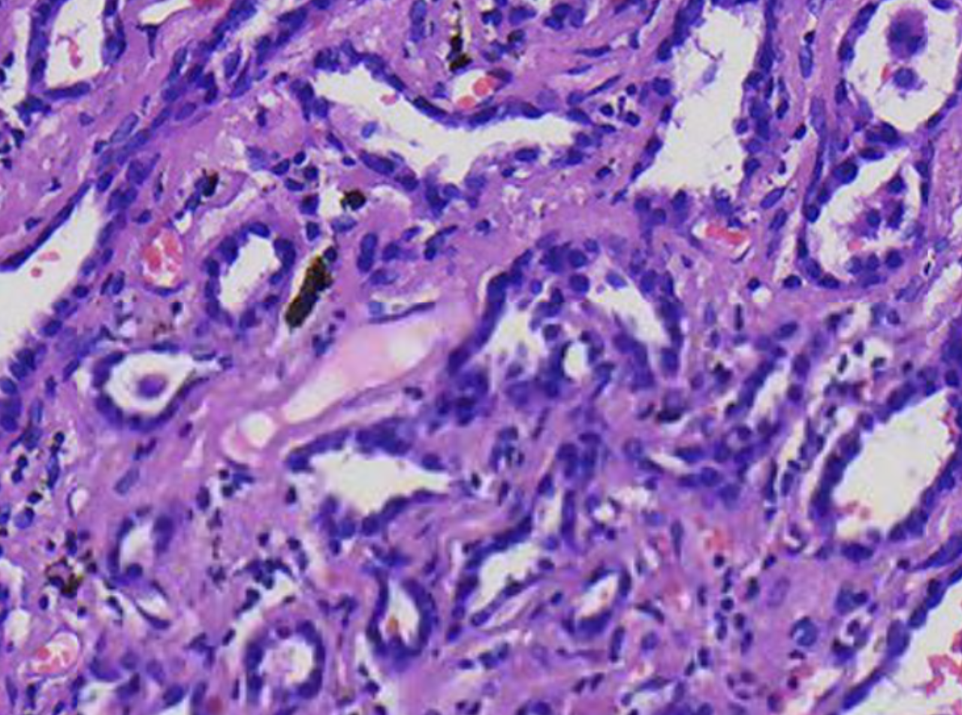

HE诊断和鉴别诊断

浸润性腺癌 腺泡为主型/WHO分级:2级

鉴别:支气管腺瘤

最终病理诊断

(右肺上叶)浸润性腺癌 非黏液型/WHIO分级:2级,表达p63.